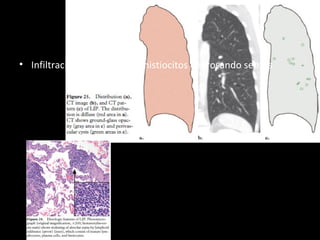

• 61.

IIP raras LIP • Benigna •Idiopática es rara • Asociada a SS, VIH, enferemedad autoinmune tiroides, enfermedad de castleman M, 50 Disnea tos, fiebre artralgias, 80% disproteinemias igG igM

• 62.

• Infiltración delinfocitos e histiocitos engrosando septos

• 63.

LIP CT • Vidrioesmerilado • Nódulos • Engrosamiento septos y peribroncovascular • *Quistes 80% LI DD: NSIP celular • DD: histiocitosis de langerhans, linfangioleiomiomatosis, enfisema, DIP,